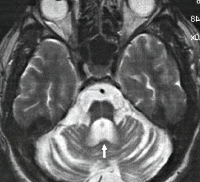

Первичная неврологическая диагностика (Эхо-ЭГ, ЭЭГ, РЭГ) не дает специфичных признаков, ее результаты могут быть в пределах нормы. КТ и МРТ головного мозга выявляет дегенерацию червя мозжечка и покрышки моста. Типичным признаком является выраженное расширение IV желудочка на фоне относительной сохранности мозжечковой коры.